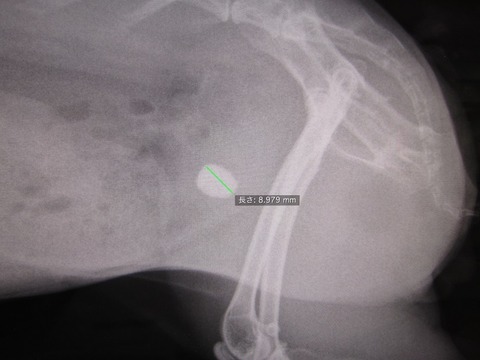

8.9てぇ!めちゃデカなってるし!

すんごい早くない?あまりにデカなるの早すぎひん

そして、膀胱内には溜まる砂はほとんど確認されない…。

膀胱に入り次第すぐ固まるんかいな

一番最初の手術で摘出した結石よりほんの少し小さいくらいでほぼ同じ大きさ。